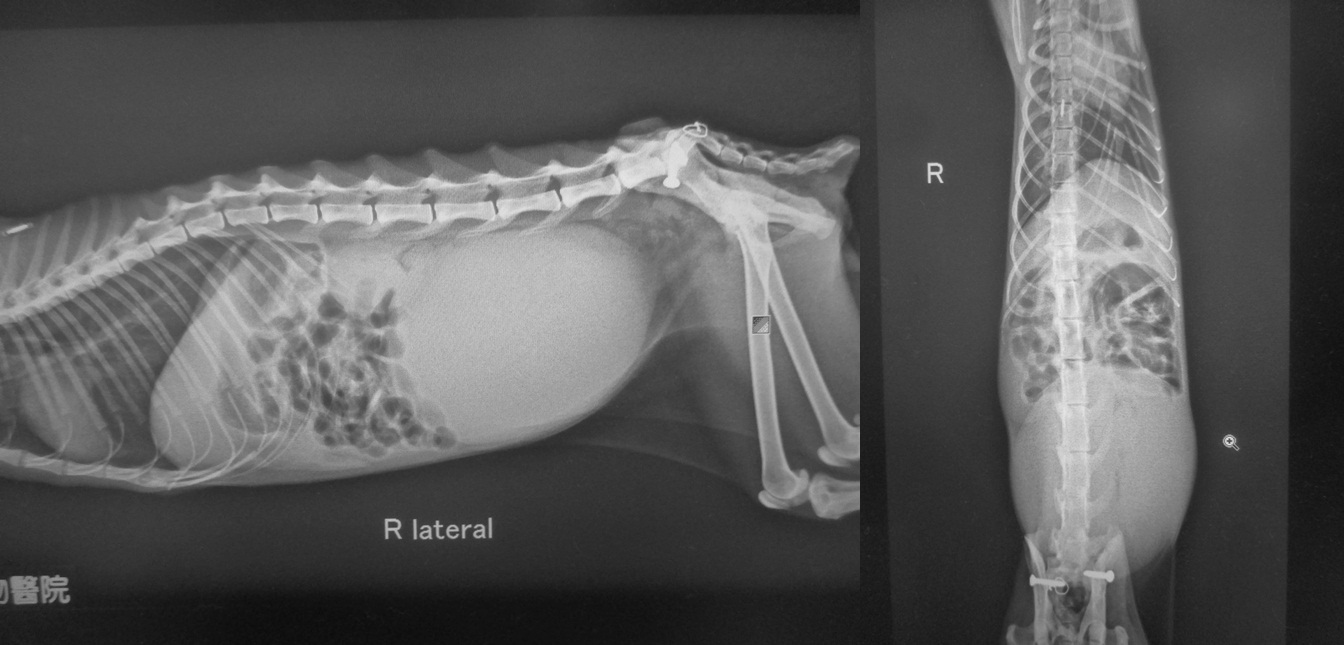

主題: 鼓山需導尿的齒齦炎貓 申請者姓名: 劉素鳳 花色: 申請日期: 2019-02-13 11:20:27 申請者部落格: 申請者臉書網址: https://www.facebook.com/sufeng.liu 所在縣市/合作醫院: 高雄市/樂生動物醫院 治療費用: 18350元 需求人數: 40人 已結案 (2024-05-31 18:36:53) 報名人員: Chia-yu Michelle Mei(已付款)、于頎亞(已付款)、黃琦珊(已付款)、Fidji Chen(已付款)、Angel Lin(已付款)、陳安 x2(已付款)、周星星(已付款)、Jasmine Lin(已付款)、Kitty Chen x2(已付款)、wgs(已付款)、Daniel Tsai x2(已付款)、心桓 x2(已付款)、Claire Huang x2(已付款)、Bella Chen、Bella Chen x2(已付款)、何偉靖(已付款)、chiawei(已付款)、ChrisLin x2(已付款)、Rachel Hsieh x2(已付款)、Elsalu(已付款)、bestlco x12(已付款)、En Rong Shen(已付款)、 候補人員: 動物病情說明: 這隻醫助母貓,貓咪呈現排尿困難,膀胱脹大,且消瘦,口腔有口炎及齒齦炎,此外貓咪還有打噴嚏及鼻分泌物等鼻氣管炎症狀,初步驗血白血球偏高有脫水.

貓咪入院時 醫院先鎮靜導尿放置導尿管及輸液給藥,並作膀胱穿刺取尿. 還有配合氣霧治療.

幫貓咪檢查時還有發現口炎, 也洗牙拔牙做了治療.

動物近況說明: 住院期間也觀察貓咪的狀況和血液監控看看貓咪復原的狀況, 待指數狀況穩定讓貓咪出院.

目前安置並照顧中. 感謝大家幫助這隻貓咪.